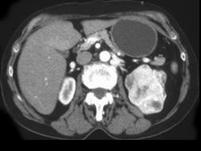

问题 男,54岁,左侧腰痛伴间断性血尿2 月余,请结合CT图像,选择最可能诊断 ( )

选项 A、左侧嗜铬细胞瘤 B、左侧肾盂癌 C、左侧肾血管平滑肌脂肪瘤 D、左侧肾上腺腺癌 E、左侧肾癌

答案 E